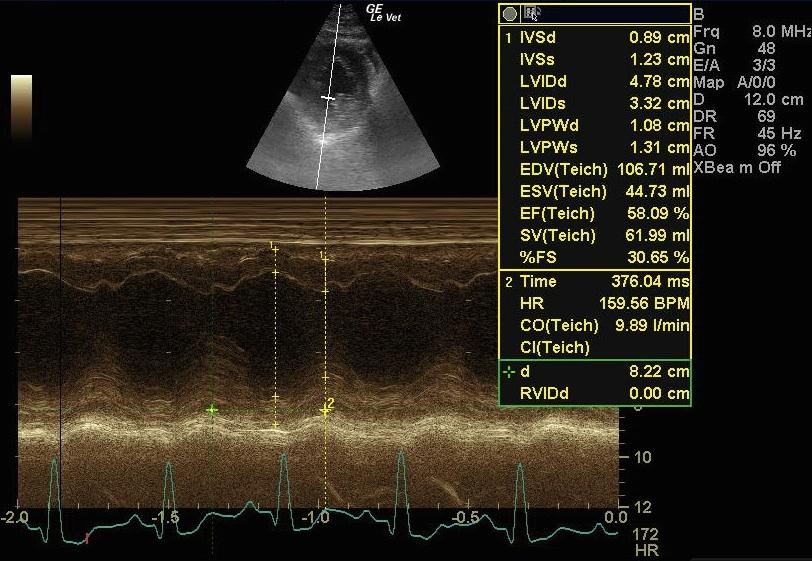

A 10-year-old NM Pit bull terrier was presented for follow up examination as a previous echocardiogram had shown thickened mitral valves. Currently there were no clinical signs. the physical exam revealed a III/VI left sided heart murmur in the mitral region.

This patient has a slightly volume loaded left ventricle, a mildly enlarged left atrium, and a normal right ventricle and atrium. The mitral valve leaflets are moderately thickened but there is no significant prolapse noted. The tricuspid valve leaflets are slightly thickened as well. There is mild mitral insufficiency and very slight tricuspid insufficiency on CDI.

DVD both AV valves. Mild MI. Slight LAE. Compensated stage b1 valvular disease.

No therapy is indicated. The patient should be rechecked every 6-9 months.